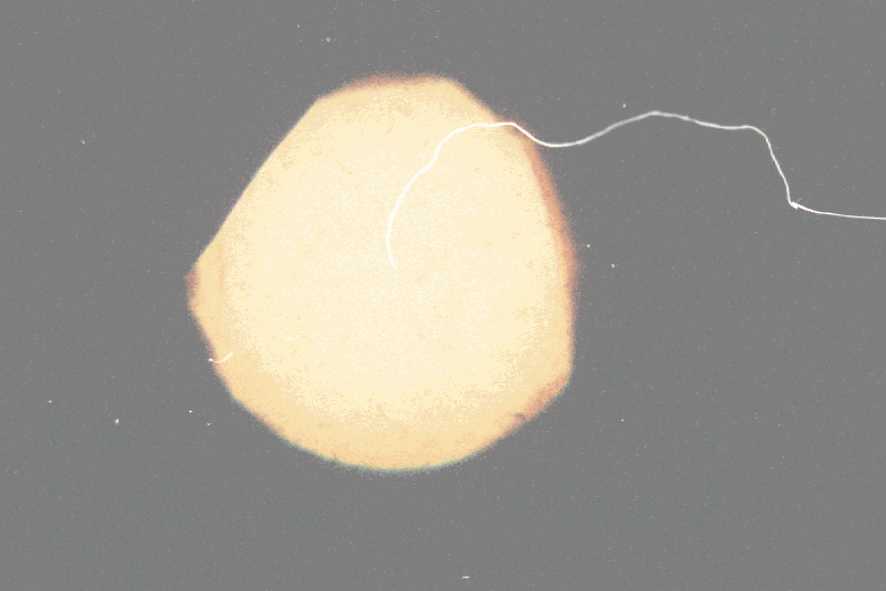

ausgehend vom Randbereich auf (vgl. Bild 2).

Linsenbrüche im Randbereich werden

häufig nicht als Beeinträchtigung wahrgenommen. Diese Schäden

führen im Reparaturfall zu Diskussionen über die korrekte Einstufung

in die einzelnen Reparaturklassen ("Die Optik war doch nicht blind, das

hätte ich doch gesehen Ein Linsenbruch kann also gar nicht vorgelegen

haben").

Ein massiv ausgeprägter Linsenbruch

ist auf dem Deckblatt abgebildet. Solche Schadensbilder sind nicht zu übersehen.

Diese Optiken werden als "blind" bezeichnet.

Bild 3: Typisches Schadensbild

einer altersgemäß verschlissenen und eingetrübtenOptik

(weil trübe) einzuschätzen ist. Des typische Bild des Inneren

einer einer trüben Optik zeigt Bild 3.